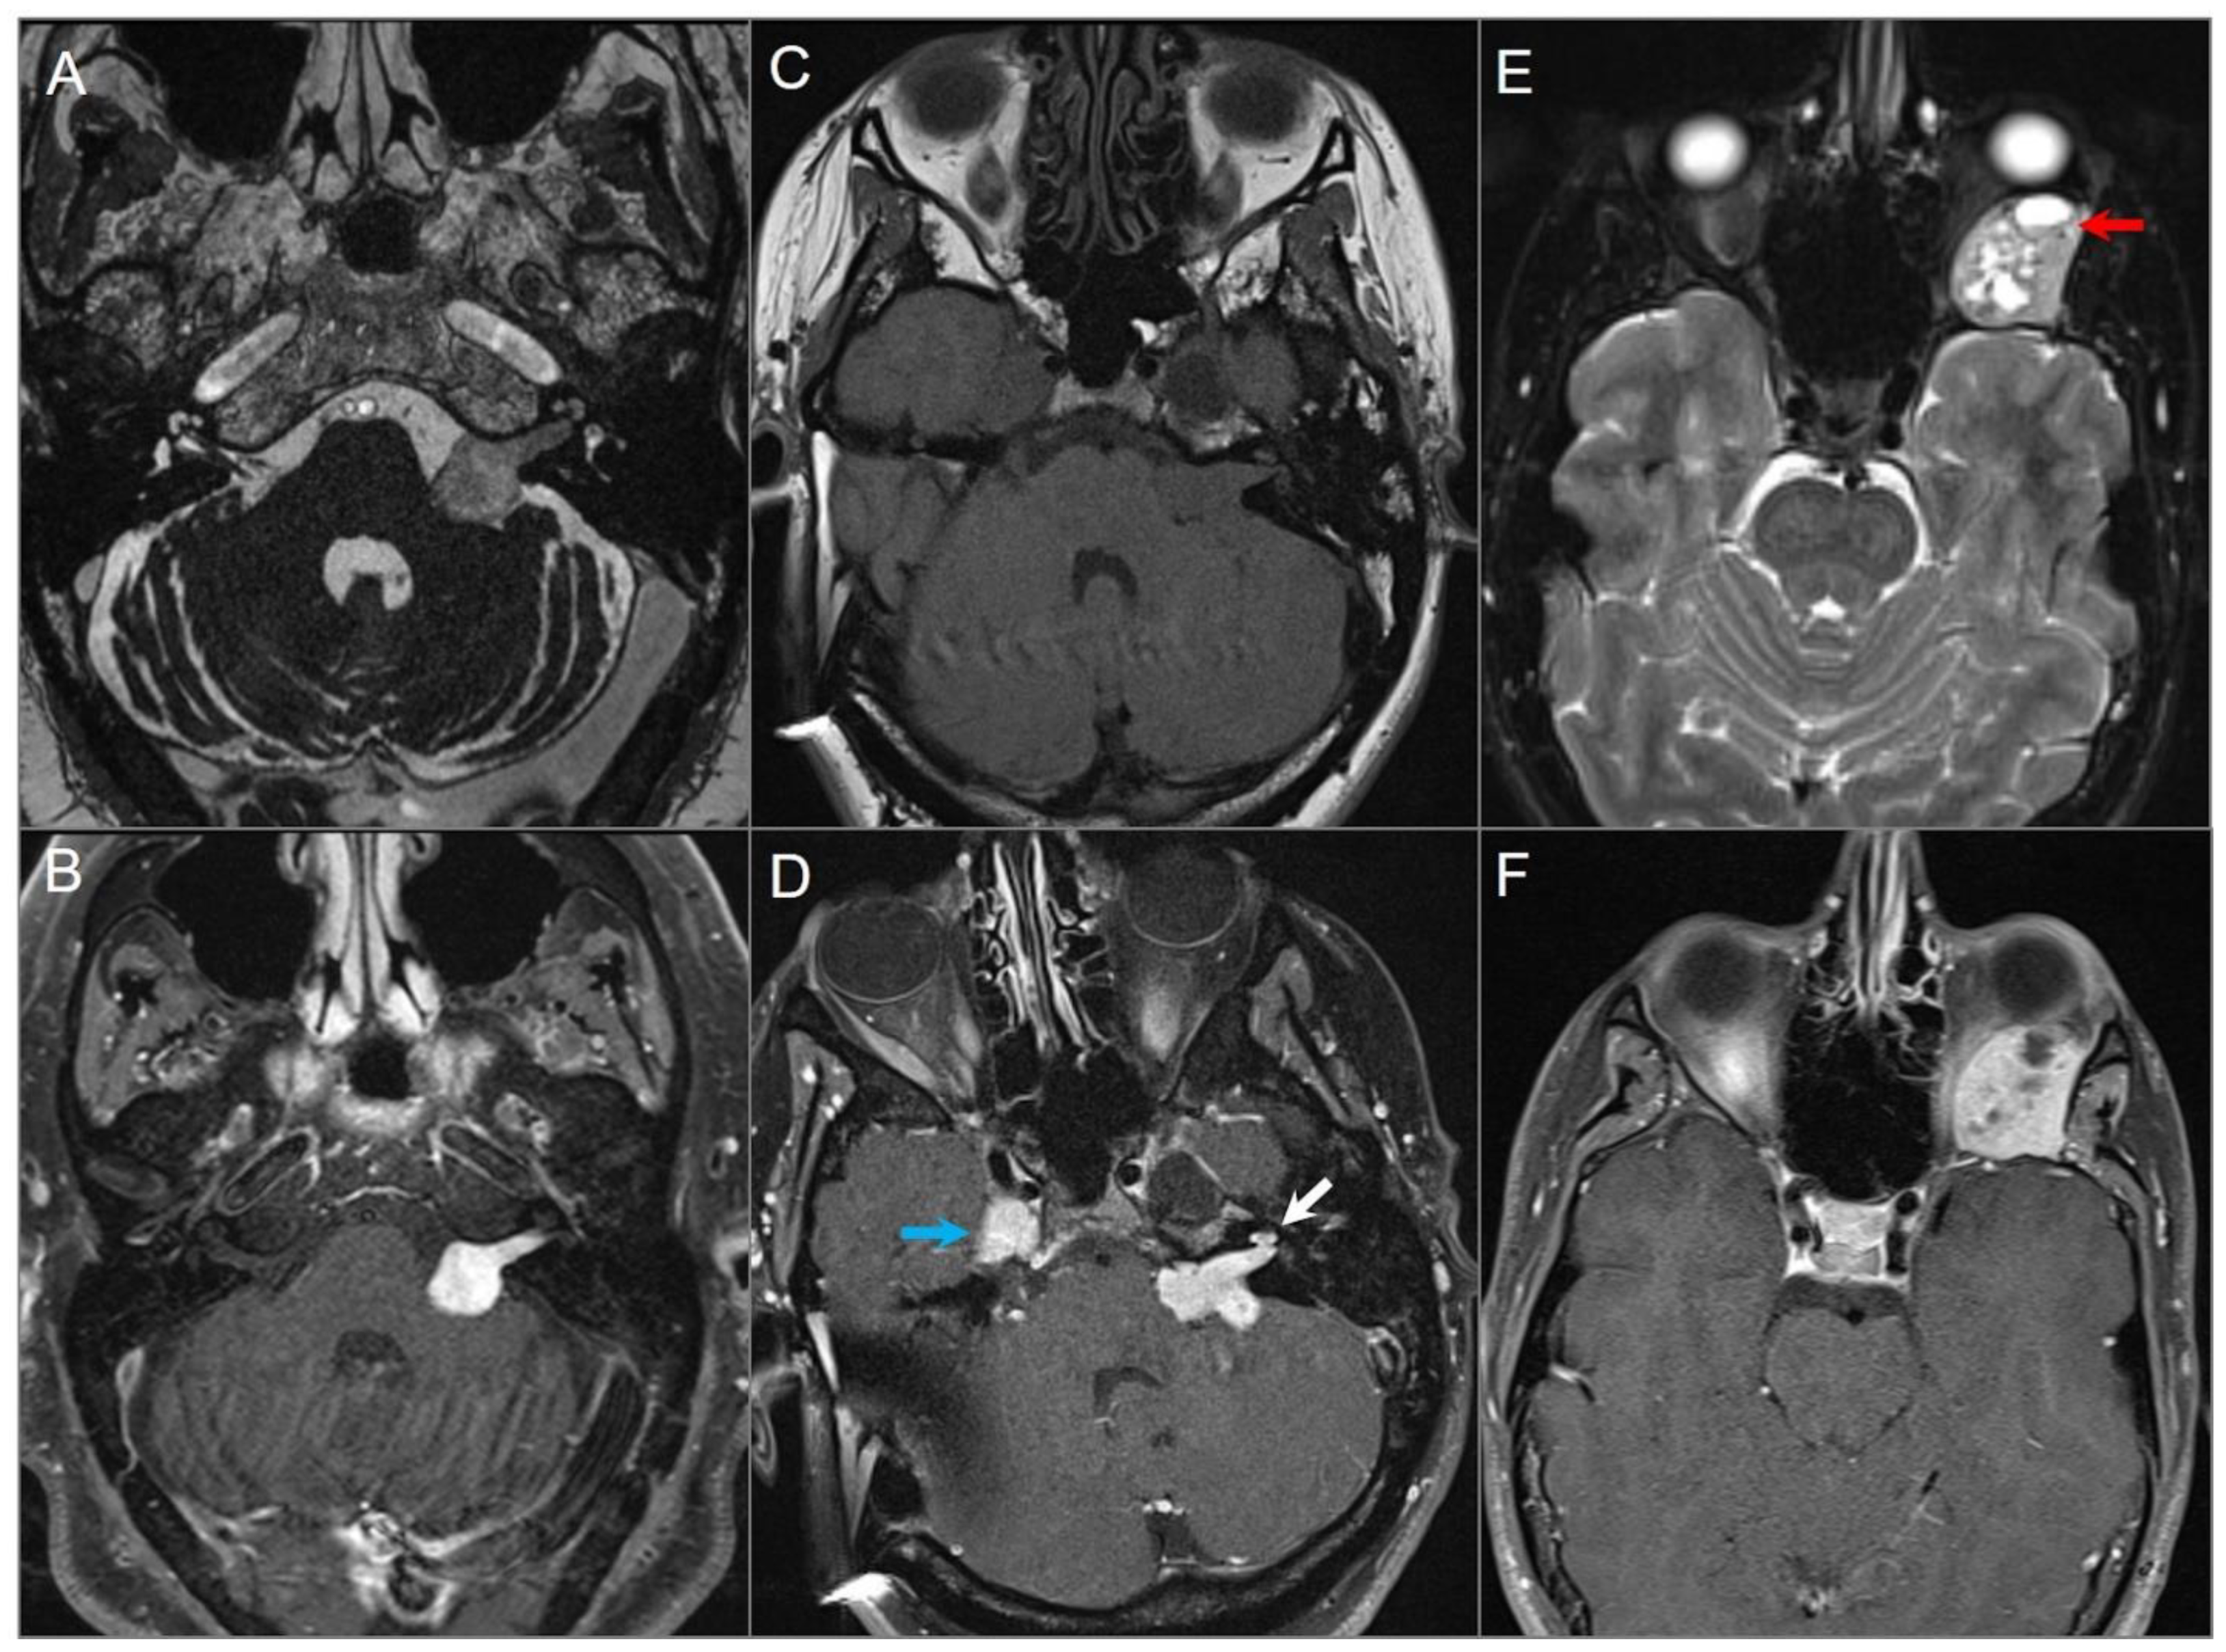

4.4.4. Endolymphatic Sac Tumor

4.4.5. Paraganglioma